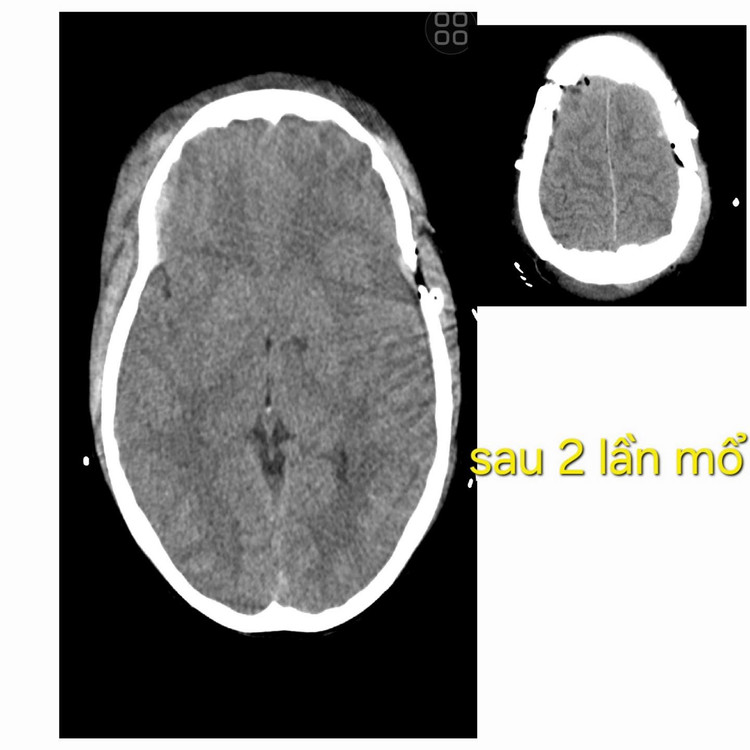

Sau khoảng 3 giờ hồi sức, bệnh nhân được chủ động chụp phim kiểm tra lần hai. Kết quả cho thấy có tụ máu ngoài màng cứng ở phía đối bên. Bệnh nhân nhanh chóng được chỉ định phẫu thuật lần hai để lấy máu tụ.

2-lan-mo-nao-3.jpg

Hết máu tụ sau 2 lần mổ - Ảnh BVCC